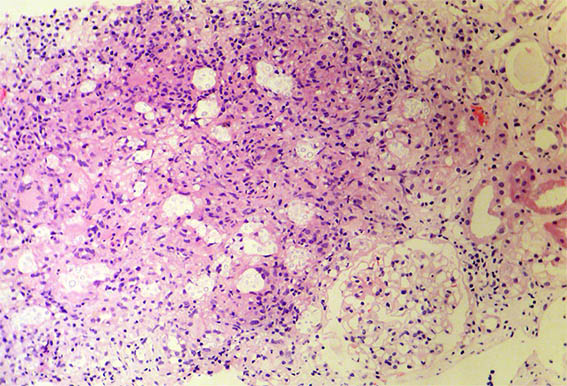

The patient is a 42-year-old man with acute kidney injury of unclear aetiology, creatinine 3.5 mg/dL, BUN: 54 mg/dL; edema in lower limbs, one week of evolution. He does not report other symptoms. As relevant history, the patient was diagnosed with HIV infection 20 days earlier and started antiretroviral therapy 2 weeks ago, which raises the possibility of acute tubulointerstitial nephritis secondary to drugs.

Look at the images of the renal biopsy:

Figure 1. H&E, X200.